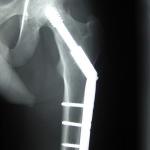

Fractures in the elderly result in significant dysfunction, with many not recovering their full function, with up to 25% requiring permanent institutional care and an eightfold increase in mortality within three months of a hip fracture.

Physicians, especially surgeons, to provide meaningful information to patients continue to look for risk factors associated with complications and death.